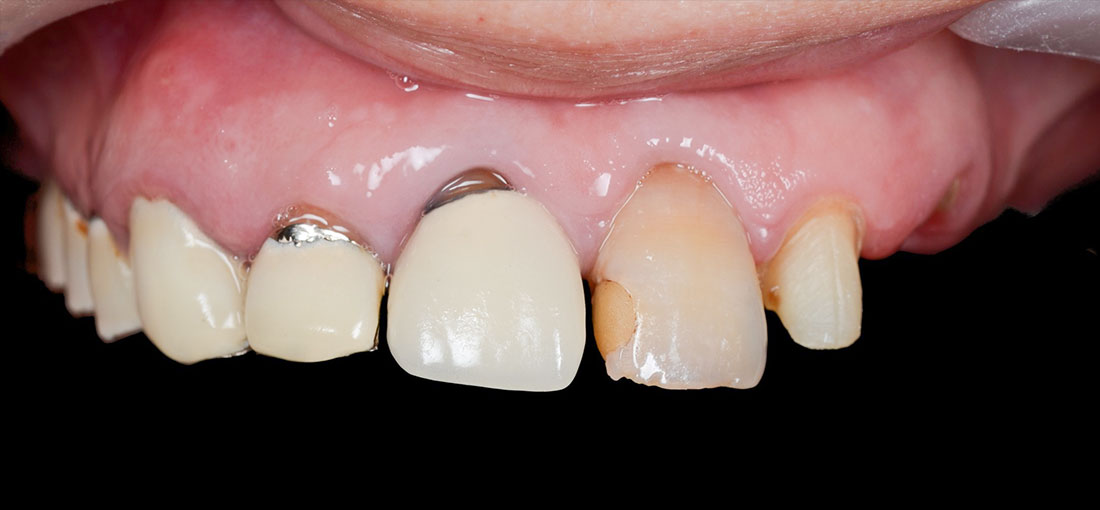

ご相談内容

- 歯の形と見た目が気になる

- 真っ白ではなく色を元の歯の色に合わせてほしい

治療内容

今回は着色したジルコニアを選択しました。

治療後

着色した被せ物を使うことでとても自然な仕上がりになりました。